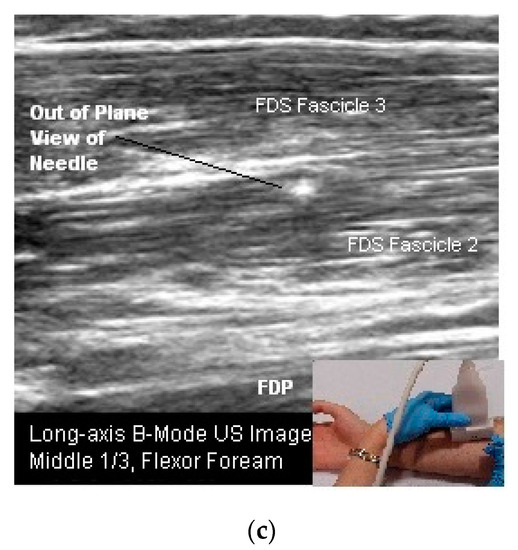

- Skeletal muscle: The sonoacoustic appearance of muscle is a mix of hyperechoic intramuscular connective tissue and hypoechoic contractile fascicles. In long axis or longitudinal view, the contractile elements and connective tissue of skeletal muscles appear as hypoechoic or hyperechoic linear bands or streaks. In transverse view, the muscle has a speckled hypo/hyperechoic appearance from the mix of contractile fascicles and connective tissue viewed in short axis [47,48,49,50]. Figure 1a,b.

- Nerves: are less hyperechoic or fibrillar than tendon. With a high frequency transducer (≥12 mHz), nerves fascicles can be visualized. In longitudinal view, the epineurium will appear hyperechoic compared to the relatively hypoechoic nerve fascicles giving the nerve the appearance of a “railroad track”. In transverse view the relatively hyperechoic epineurium surrounds the hypoechoic fascicles giving the nerve a speckled appearance [49,51] (Figure 2a,b).